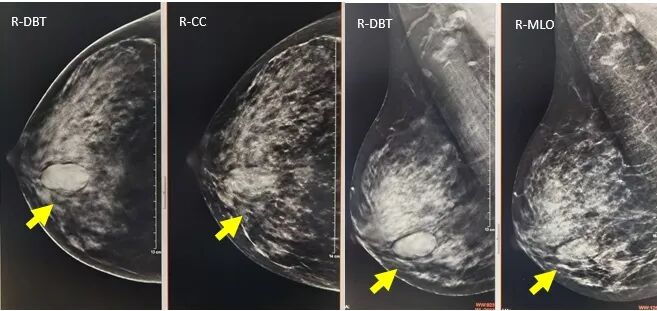

1.肿块的显示

病例2:CC,MLO/DBT显示:肿块、形态、边缘、密度、大小显示显著优于MG,特别是肿块周围晕环显示清晰,对于良恶性病变的鉴别颇具意义。病理:乳腺纤维腺瘤。